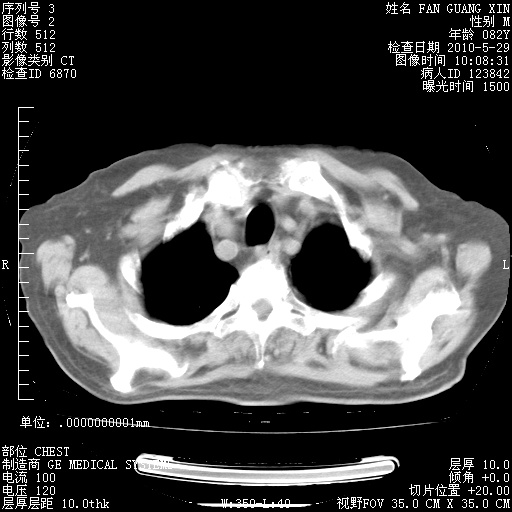

治疗3周后的肺部CT纵隔窗

从胸部影像学来看,的确有好转。至于目前为何发热不甚清楚?除了发热还有其他症状如有无喀痰,痰呈丝状吗?等等。尽量搜寻有无致发热其它可能原因?真菌?其它?如果的确无其他致发热的原因,考虑将甲强龙调至60-80mg bid/日。免疫全套基本无异常,考虑多系特发性肺间质纤维化